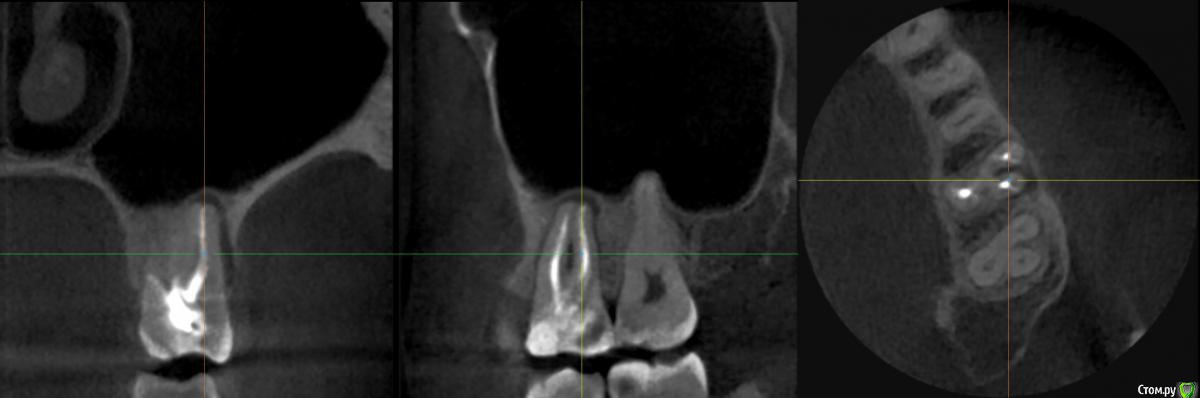

26 зуб, лечили лет 6 назад, стоит штифт в канале который "внутрь". с тех пор до недавнего времени не беспокоил. где-то месяц назад появился свищ над зубом, с внешней стороны. судя по кт - воспаление вокруг "внешнего" корня со стороны семерки.

делали несколько плоских снимков, но на них ничего внятного не увидели, кроме того что каналы запломбированы хорошо (на руках у меня этих снимков нет).

на верхней поверхности зуба со стороны семерки, примерно посередине, обнаружили трещину, немного препарировали, насколько глубоко идет достоверно не известно

есть КТ, что именно оттуда лучше показать - не знаю, срезы примерно в интересующей области